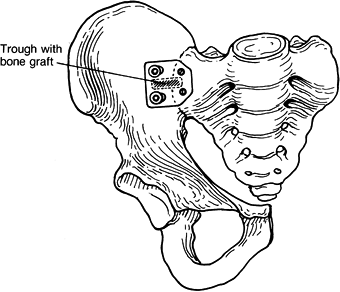

Make a trough over the sacroiliac joint

in its central portion. Obtain a graft from the anterior portion of the

ipsilateral iliac wing and use it to fill the trough across the

sacroiliac joint. -

Place the sacroiliac joint plate over the

trough and secure it with 6.5-mm cancellous screws in the sacrum and

cortical screws in the iliac wing (Fig. 28.10). Use a flexible drill to make the holes.

Figure 28.10. Right hemipelvis with fusion of the sacroiliac joint showing the bone graft and plate placement. -